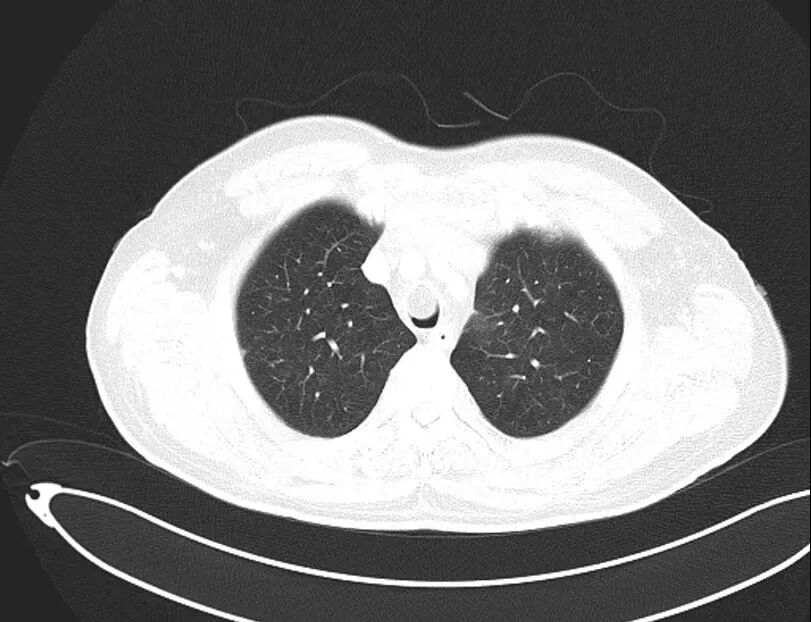

CT檢查影像

“這個腫物已經把他的氣道堵的只剩下一條縫了,如果這個時候老人家一口痰上來,那就可能全部堵住,分分鐘可能窒息而亡,必須盡快進行介入檢查和手術。”毛列龍醫(yī)生介紹道。